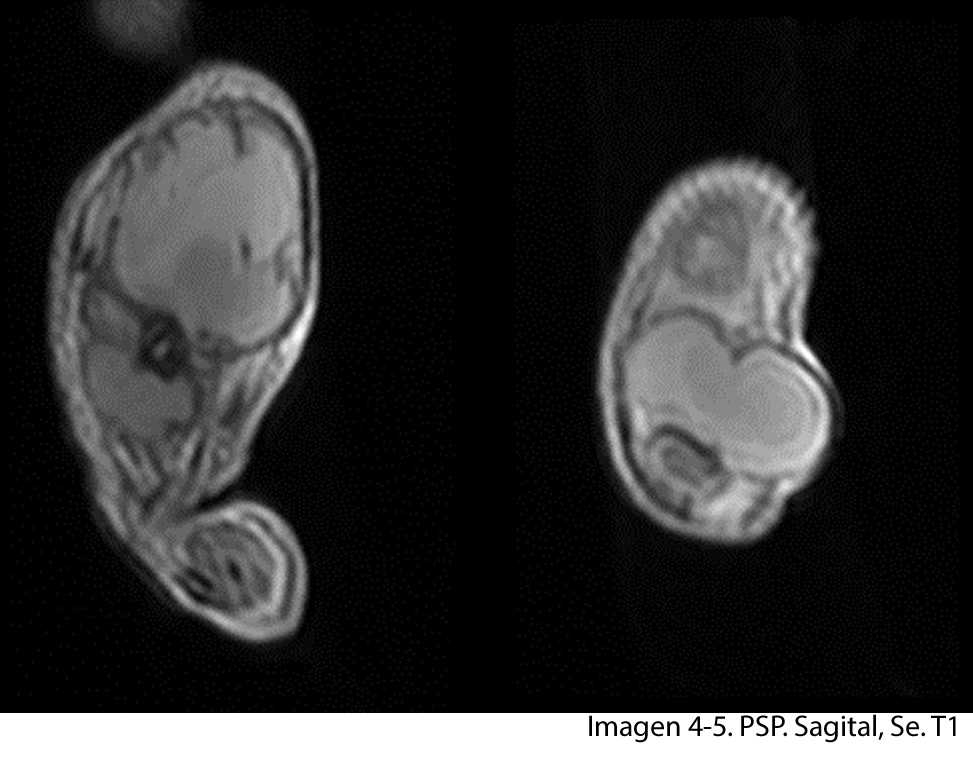

A nivel del muslo izquierdo se observa una colección bilobulada, en la parte proximal se observa imagen que mide 7.05 x 7.17 cms en el tercio distal se observa imagen que mide 3 x 4.01 cms. En la ponderación T2 la lesión se vuelve hiperintensa y en la ponderación T1 con mdc la lesión se vuelve hipointensa con realce de la periferia, lo que confirma la presencia de absceso.

La diáfisis femoral proximal se ve totalmente destruida, a nivel del hombro izquierdo la cabeza del humero no se observa.

• ABSCESO A NIVEL DEL MUSLO IZQUIERDO

• OSTEOMIELITIS DEL FÉMUR IZQUIERDO